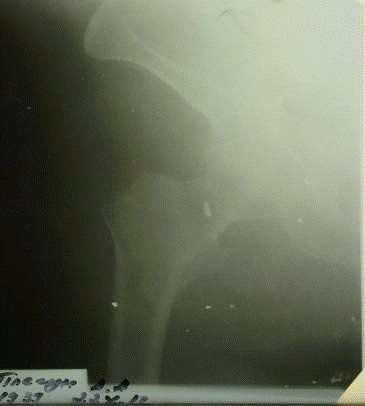

.        Рентгенография костей таза:

От 16.10.2013г.

Заключение: в прямой и боковой проекции правого бедра определяется чрезвертельный перелом правой бедренной кости со смещением фрагментов.

От 22.10.2013г.

Заключение: в прямой и боковой проекции правого бедра определяется чрезвертельный перелом правой бедренной кости в условии скелетного вытяжения. Отломки фиксированы без смещения. Функциональная ось правильная.

Вывод: Динамика рентгенограмм без видимых изменений.